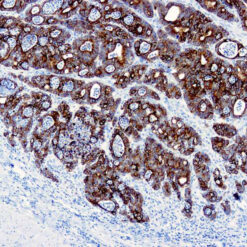

Leukocyte Common Antigen (LCA)/CD45

CD45R, also designated CD45 and PTPRC, has been identified as a transmembrane glycoprotein, broadly expressed among hematopoietic cells. Multiple isoforms of CD45R are distributed throughout the immune system according to cell type. These isoforms arise because of alternative splicing of exons 4, 5, and 6. The corresponding protein domains are characterized by the binding of monoclonal antibodies specific for CD45RA (exon 4), CD45RB (exon 5), CD45RC (exon 6) and CD45RO (exons 4 to 6 spliced out). The variation in these isoforms is localized to the extracellular domain of CD45R, while the intracellular domain is conserved. CD45R functions as a phosphor-tyrosine phosphatase. Antibody to CD45 is useful in differential diagnosis of lymphoid tumors from non-hematopoietic undifferentiated neoplasms.

| Positive Control Tissue | Tonsil |